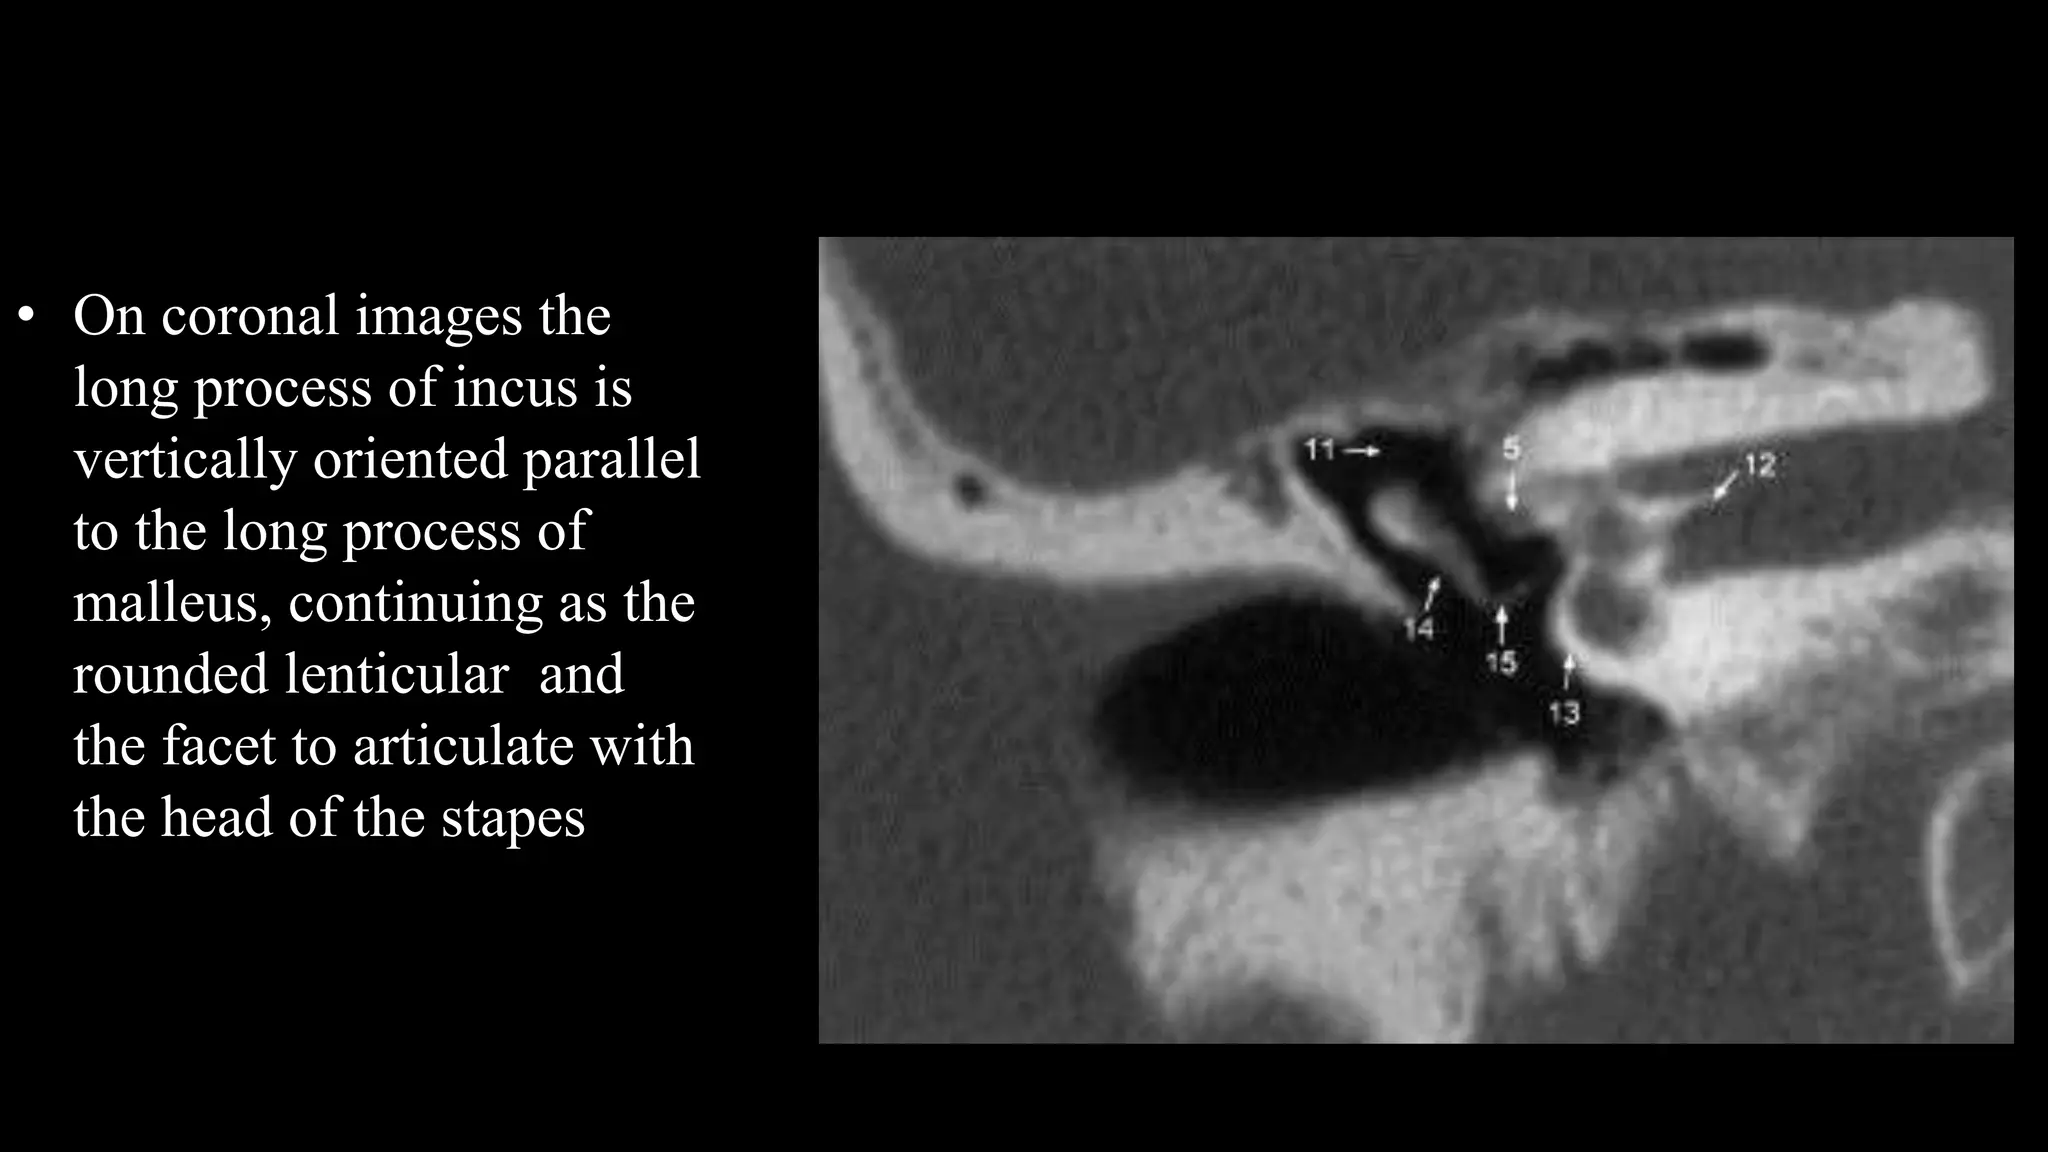

• On coronal images the

long process of incus is

vertically oriented parallel

to the long process of

malleus, continuing as the

rounded lenticular and

the facet to articulate with

the head of the stapes